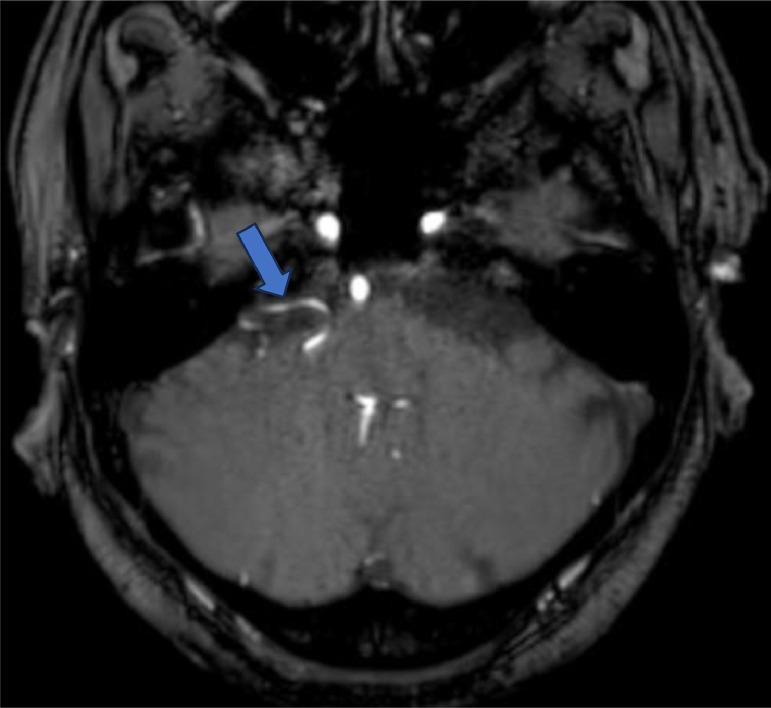

The highly variable anatomy of the anterior inferior cerebellar artery is one of the causative factors of neurovascular compression of the facial and vestibulocochlear nerve resulting in hemifacial spasms associated with hearing loss, vertigo, and tinnitus. Our patient a 64-year-old male presented with such complaints for the past few months. He was investigated thoroughly for the cause and on Magnetic resonance imaging of the brain with Fast imaging employing steady-state acquisition sequence it was evident that the anterior inferior cerebellar artery loop was compressing the seventh and eighth cranial nerves on the right side. This was responsible for the patient's symptoms. He also had sensorineural hearing loss in the right ear. He was started on symptomatic treatment as he denied any surgical intervention.

小脑下前动脉高度可变的解剖结构是导致面听神经血管受压,进而引发伴有听力丧失、眩晕和耳鸣的半面痉挛的致病因素之一。我们的患者是一名64岁男性,在过去几个月里出现了上述症状。对其病因进行了全面检查,采用稳态采集序列的快速成像进行脑部磁共振成像检查时,明显发现小脑下前动脉襻压迫右侧第七和第八颅神经。这就是导致患者症状的原因。他右耳还存在感音神经性听力损失。由于他拒绝任何手术干预,所以开始了对症治疗。